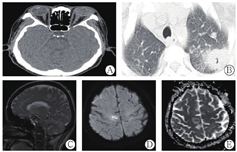

患者女性,58岁,主因"发现HBsAg阳性8年,间断腹胀1年,高热、左眼失明6 d"于2019年6月29日就诊于我院肝病科。既往有左前臂外伤手术史及乙型肝炎家族史。入院6 d前突发高热,伴左眼疼痛、头痛,左眼视力急剧下降至完全失明。查体皮肤巩膜中度黄染,左眼大量脓性分泌物,下腹部压痛,移动性浊音可疑。入院检查肝功能异常,PTA 19%,HBV DNA 2.9×106 IU/ml,感染指标显著升高,CD4+T淋巴细胞计数287个细胞/μl。眼内液高通量测序提示真菌、金黄色葡萄球菌、肺炎克雷伯杆菌。眼部脓性分泌物细菌培养提示金黄色葡萄球菌、肺炎克雷伯氏菌肺炎亚种。眼眶CT提示:左眼玻璃体变形、混浊,晶状体偏向上方,泪腺略肿胀,考虑眼球感染。胸部CT提示:左肺上叶炎性病变,内含厚壁空洞。头颅MRI示:右侧额叶内侧、左侧基底节小结节,考虑脑脓肿。左侧眼球变形,周围炎性改变(图3)。眼科查体左眼结膜充血,角膜水肿,前房满布黄色脓性物质,其后窥不清。主要诊断:慢加亚急性肝衰竭(MELD评分28分)、乙型病毒性肝炎慢性重度、脓毒血症、肺脓肿、脑脓肿、左眼眼内炎(细菌+真菌)、左眼角膜穿孔。给予美罗培南、万古霉素抗感染,伏立康唑抗真菌治疗,恩替卡韦抗病毒、保肝降酶、补充人血白蛋白、新鲜血浆等治疗,眼部定期清创换药,待全身情况好转、感染控制后再行左眼内容物剜除术。经治疗患者体温正常,肝功能稳定,肺部病灶较前缩小,脑脓肿病灶较前无改善,左眼球萎缩,眼科查体左眼角膜穿孔,自角膜穿孔处流出脓性物质。7月28日突发上消化道出血,后期患者要求出院。

A:眼眶CT示:左眼玻璃体变形、混浊,泪腺略肿胀;B:胸部CT示:双肺上叶多发团片影,左肺上叶内可见新月形空洞,内壁光滑;C~E:头颅增强MRI可见右侧额叶内侧异常信号结节,DWI高信号小结节,ADC中心低信号,考虑脑脓肿可能性大,图C是矢状位,图D、E是轴位